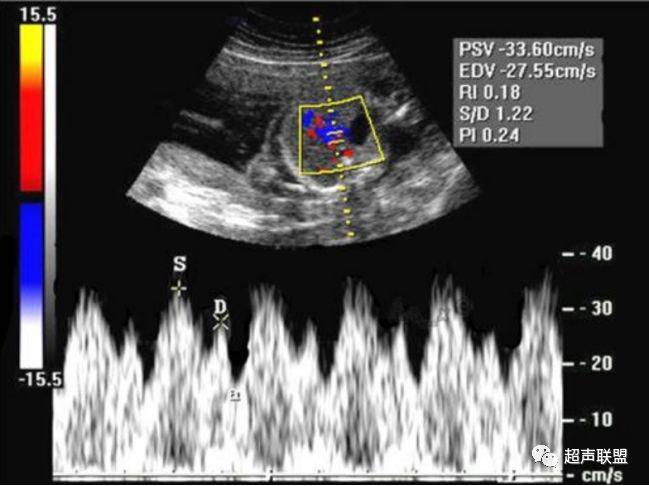

4 脐静脉频谱

胎儿宫内缺氧严重时脐静脉出现搏动。

6、脐静脉:脐静脉搏动(见于严重的胎儿宫内缺氧);

4、脐静脉搏动。

图9 脐静脉搏动